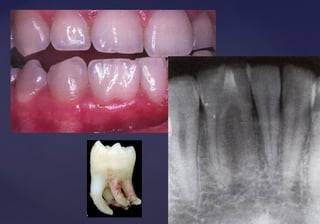

GEMINACIÓNGEMINACIÓN::

 Formación de dientesFormación de dientes

gemelos.gemelos.

 Generalmente dosGeneralmente dos

supernumerarios o unsupernumerarios o un

supernumerario con otrosupernumerario con otro

diente de la serie normal.diente de la serie normal.

 Causa: División del germenCausa: División del germen

dentario anormalmentedentario anormalmente

grande, o a un sinodontismogrande, o a un sinodontismo

(unión con gérmenes de(unión con gérmenes de

dientes vecinos)dientes vecinos)

 Frecuentes en ICS y en ILI;Frecuentes en ICS y en ILI;

dientes inftantiles.dientes inftantiles.

• Presentan continuidad de las

cámaras pulpares y de la dentina.

• Radiográficamente se observan dos

coronas conformadas con un canal

radicular.

FusiónFusión

 Unión de dos dientes de la serie normal, mediante la dentina,Unión de dos dientes de la serie normal, mediante la dentina,

independientemente de la pulpa y del esmalte.independientemente de la pulpa y del esmalte.

 Se cree que es causada por la presión o fuerza durante el desarrollo de laSe cree que es causada por la presión o fuerza durante el desarrollo de la

raíz adyacente.raíz adyacente.

 Frecuente entre incisivos central y lateral y lateral y canino de dientesFrecuente entre incisivos central y lateral y lateral y canino de dientes

temporarios.temporarios.

 Mas frecuentes en la zona mandibular anterior.Mas frecuentes en la zona mandibular anterior.